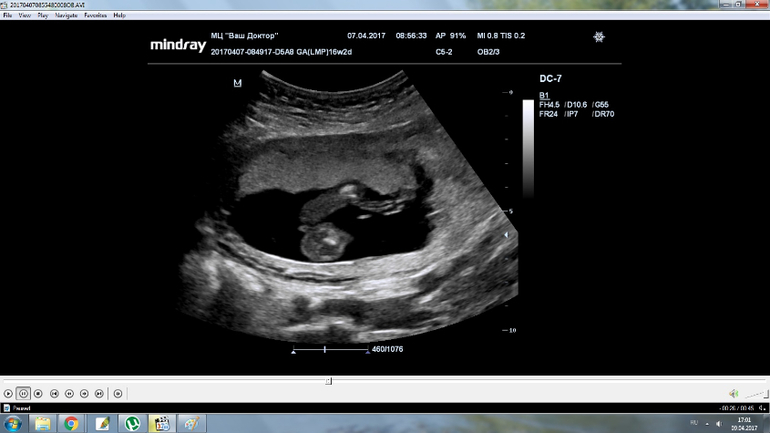

Ну девчуля же? Кто разбирается?

Пол малышаВсе 16 недель была просто уверенна, что в домике живет сыночка, а тут на УЗИ огорошили, что у нас там девица-красавица! Я конечно прибываю в небольшом шоке, но БЕЗУМНО этому рада!!!!!

Записали нам диск, все выходные пересматривала, сделала несколько фото, что скажете?